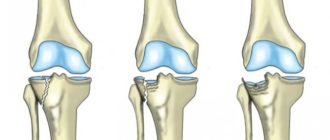

Как лечить перелом мыщелка большеберцовой кости Согласно статистике, нарушения целостности нижних конечностей встречаются довольно

Вылетает коленная чашечка Самая крупная сесамовидная кость — коленная чашечка (пателла) — широкая пластина,